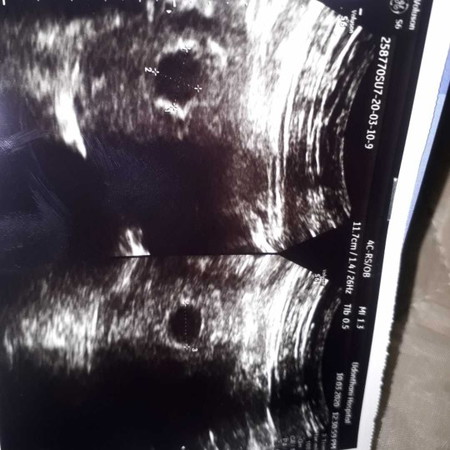

ไปซาววันนี้ ไม่เจออะไร แม่ท่านใหนตรวจไม่เจอบ่าง 6week ?

6 week ก็เจอแต่ถุงเหมือนกันครับ ไปเจอตอน 8 week พร้อมเสียงหัวใจเต้น

กำลังฝังตัวึะ ประมาน8 week.ถึง11 week เดียวก้อเจอน้องคะ ไม่ต้องกังวล

บ้านนี้เจอตอน7วีคค่ะ พร้อมเสียงหัวใจเต้น แต่น้องตัวเล็กมากๆ

คุณแม่ในเย็นๆ อย่าเพิ่งคิดมากนะคะ แม่บ้านนี้เจอน้องตอน8Wค่ะ

อย่าคิดมากนะคะ มองในแง่ดีเข้าไว้ ส่วนมากจะเริ่มเจอที่8week ค่ะ

6wไม่เจอเหมือนกันจ้า ไปซาวรอบ2วันนี้เหมือนกันเจอน้องแล้ว12w

อย่างน้อยต้อง8wคะตอนนี้น้องยังจิ้วมากคะแม่ลองซาวใหม่นะคะ